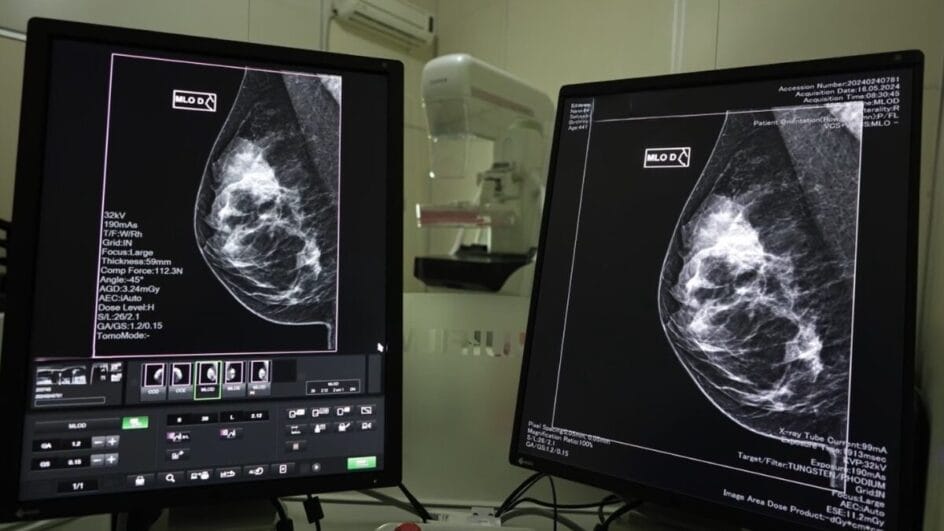

Em 2024, mais de 2,5 mil mulheres receberam o diagnóstico de câncer de mama em Santa Catarina e 167,2 mil mamografias foram realizadas pelo Sistema Único de Saúde (SUS), conforme dados da SES. Além disso, segundo a pasta, as unidades habilitadas em oncologia realizaram 613 cirurgias desta neoplasia no ano passado.

A detecção precoce do câncer de mama é fundamental para aumentar as chances de tratamentos menos invasivos e com maiores taxas de sucesso. As mamografias são realizadas pelo SUS, via Atenção Primária à Saúde, com prestadores dos municípios e Consórcios de Saúde.

Hospitais de gestão estadual, que prestam serviços de saúde da mulher e possuem mamógrafos, também realizam os exames.